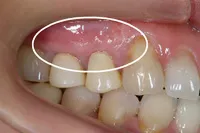

術後3ヶ月

術前に比べ、歯茎の組織が再生され、健康な状態の時とほぼ同様になりました。